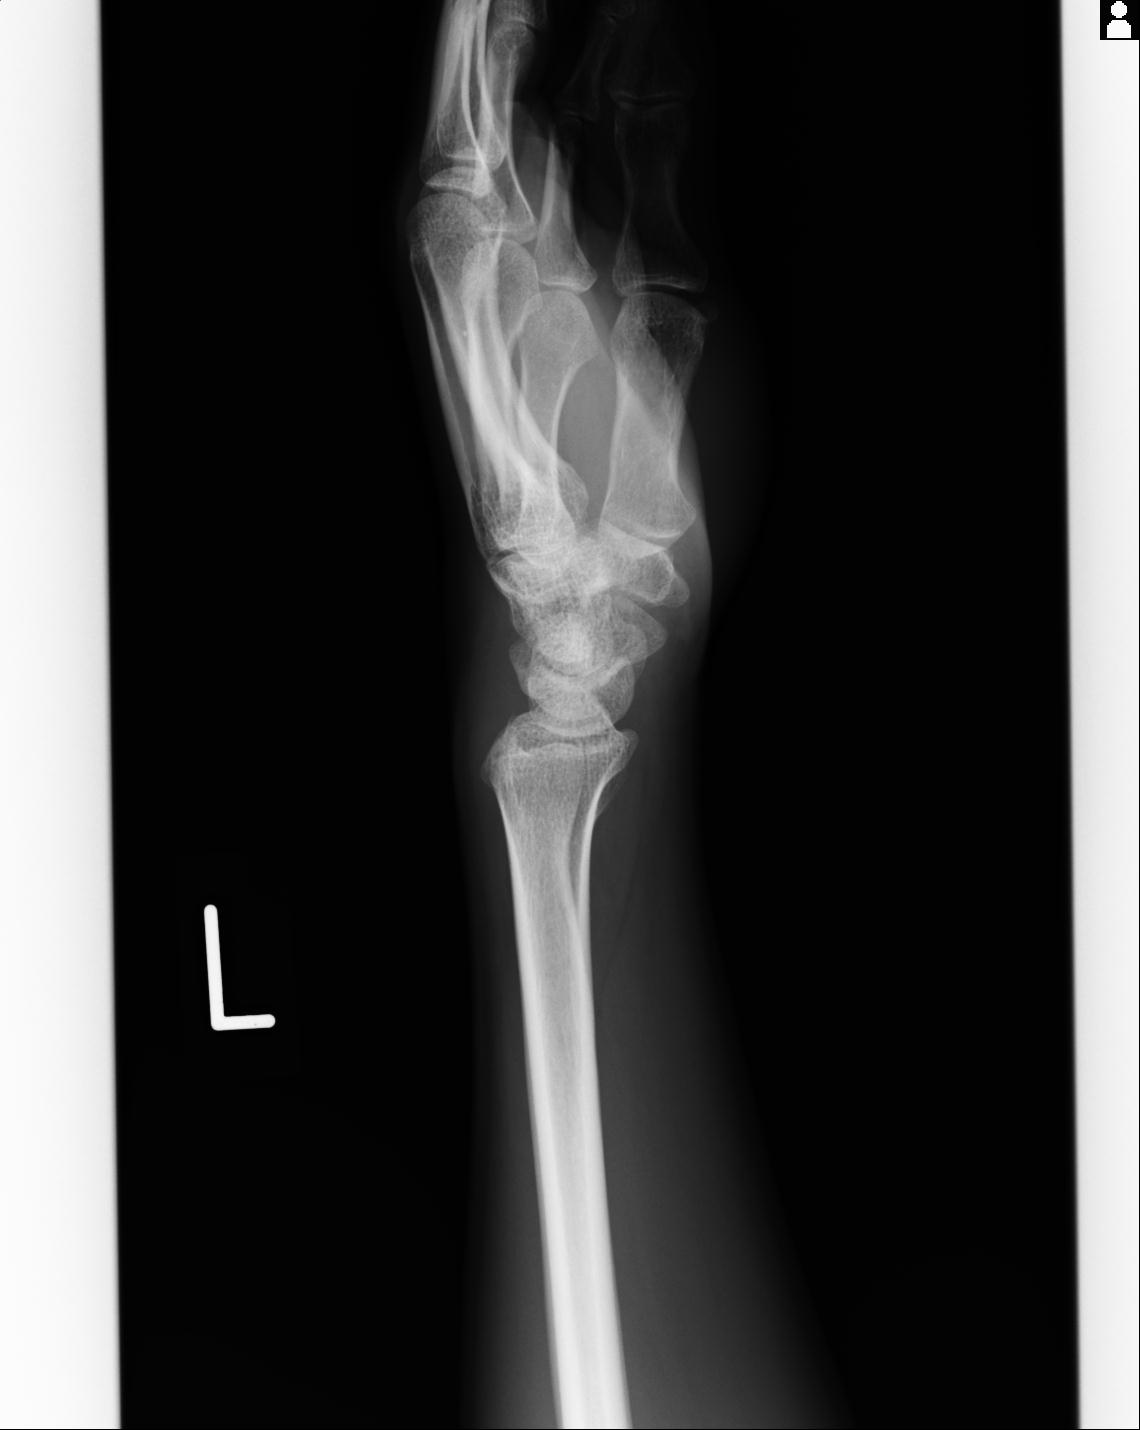

46666 1/23 両股正面+軸と右手関節 2R 76歳女性 右橈骨遠位端

46666 1/28 両股正面+軸と 1/26 右手関節 2R 76歳女性 右転子部骨折